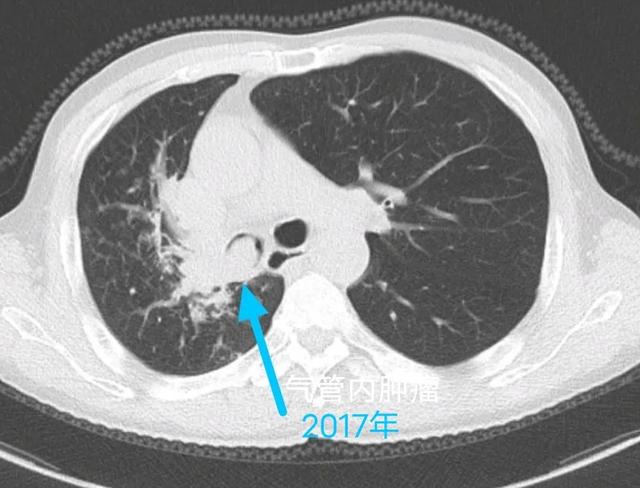

癌症从一开始就已经决定一个人的命运,治和不治都一样,是真的吗?插图3

就像这位病人是小细胞肺癌,因为发展快、转移早,查出来时就无法手术。

但他通过放化疗为主的综合治疗,目前已经带瘤生存三年半。

癌症从一开始就已经决定一个人的命运,治和不治都一样,是真的吗?插图4

这是一位中央型肺鳞癌患者,是一个老烟民,肿瘤侵犯主支气管根部,手术获益机会渺茫,选择放疗为主的综合治疗。

癌症从一开始就已经决定一个人的命运,治和不治都一样,是真的吗?插图5

这是去年年底做的复查,肿瘤萎缩残留放疗后改变,目前几乎无症状。